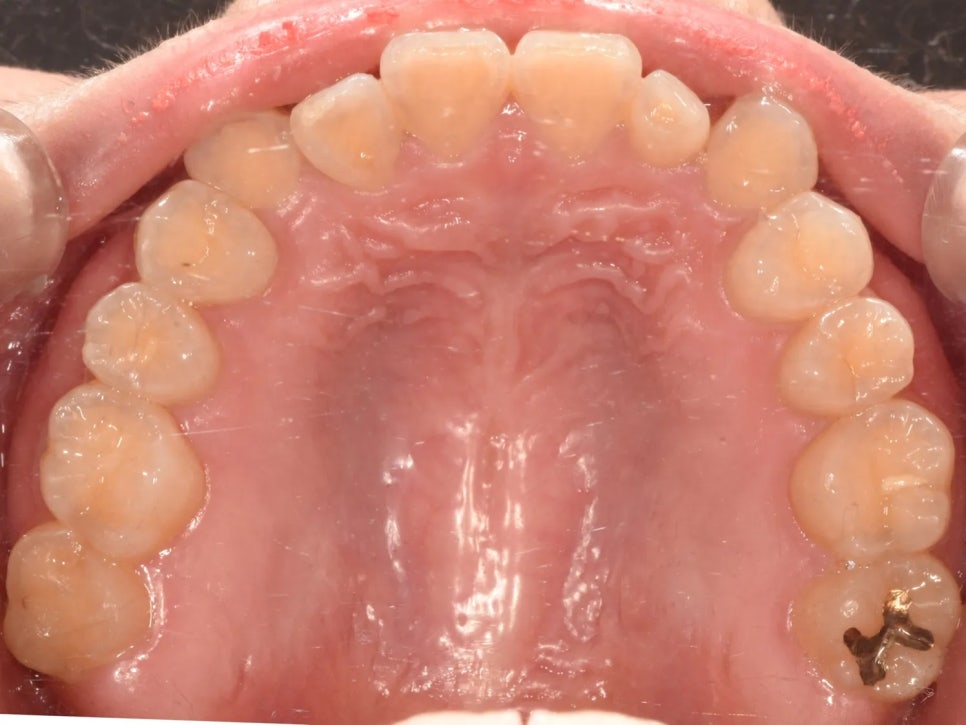

윗니를 위에서 내려다본 사진도 살펴볼게요. 여기서 중요한 포인트가 있는데요, 두 번째 앞니(측절치)가 안쪽으로 들어가 있고, 송곳니는 상대적으로 나와있는 상태였습니다. 즉 윗니들이 다 정상적으로 배열되기에는 위턱의 크기가 다소 부족하다는 것을 의미해요.

치료 전 구내 사진